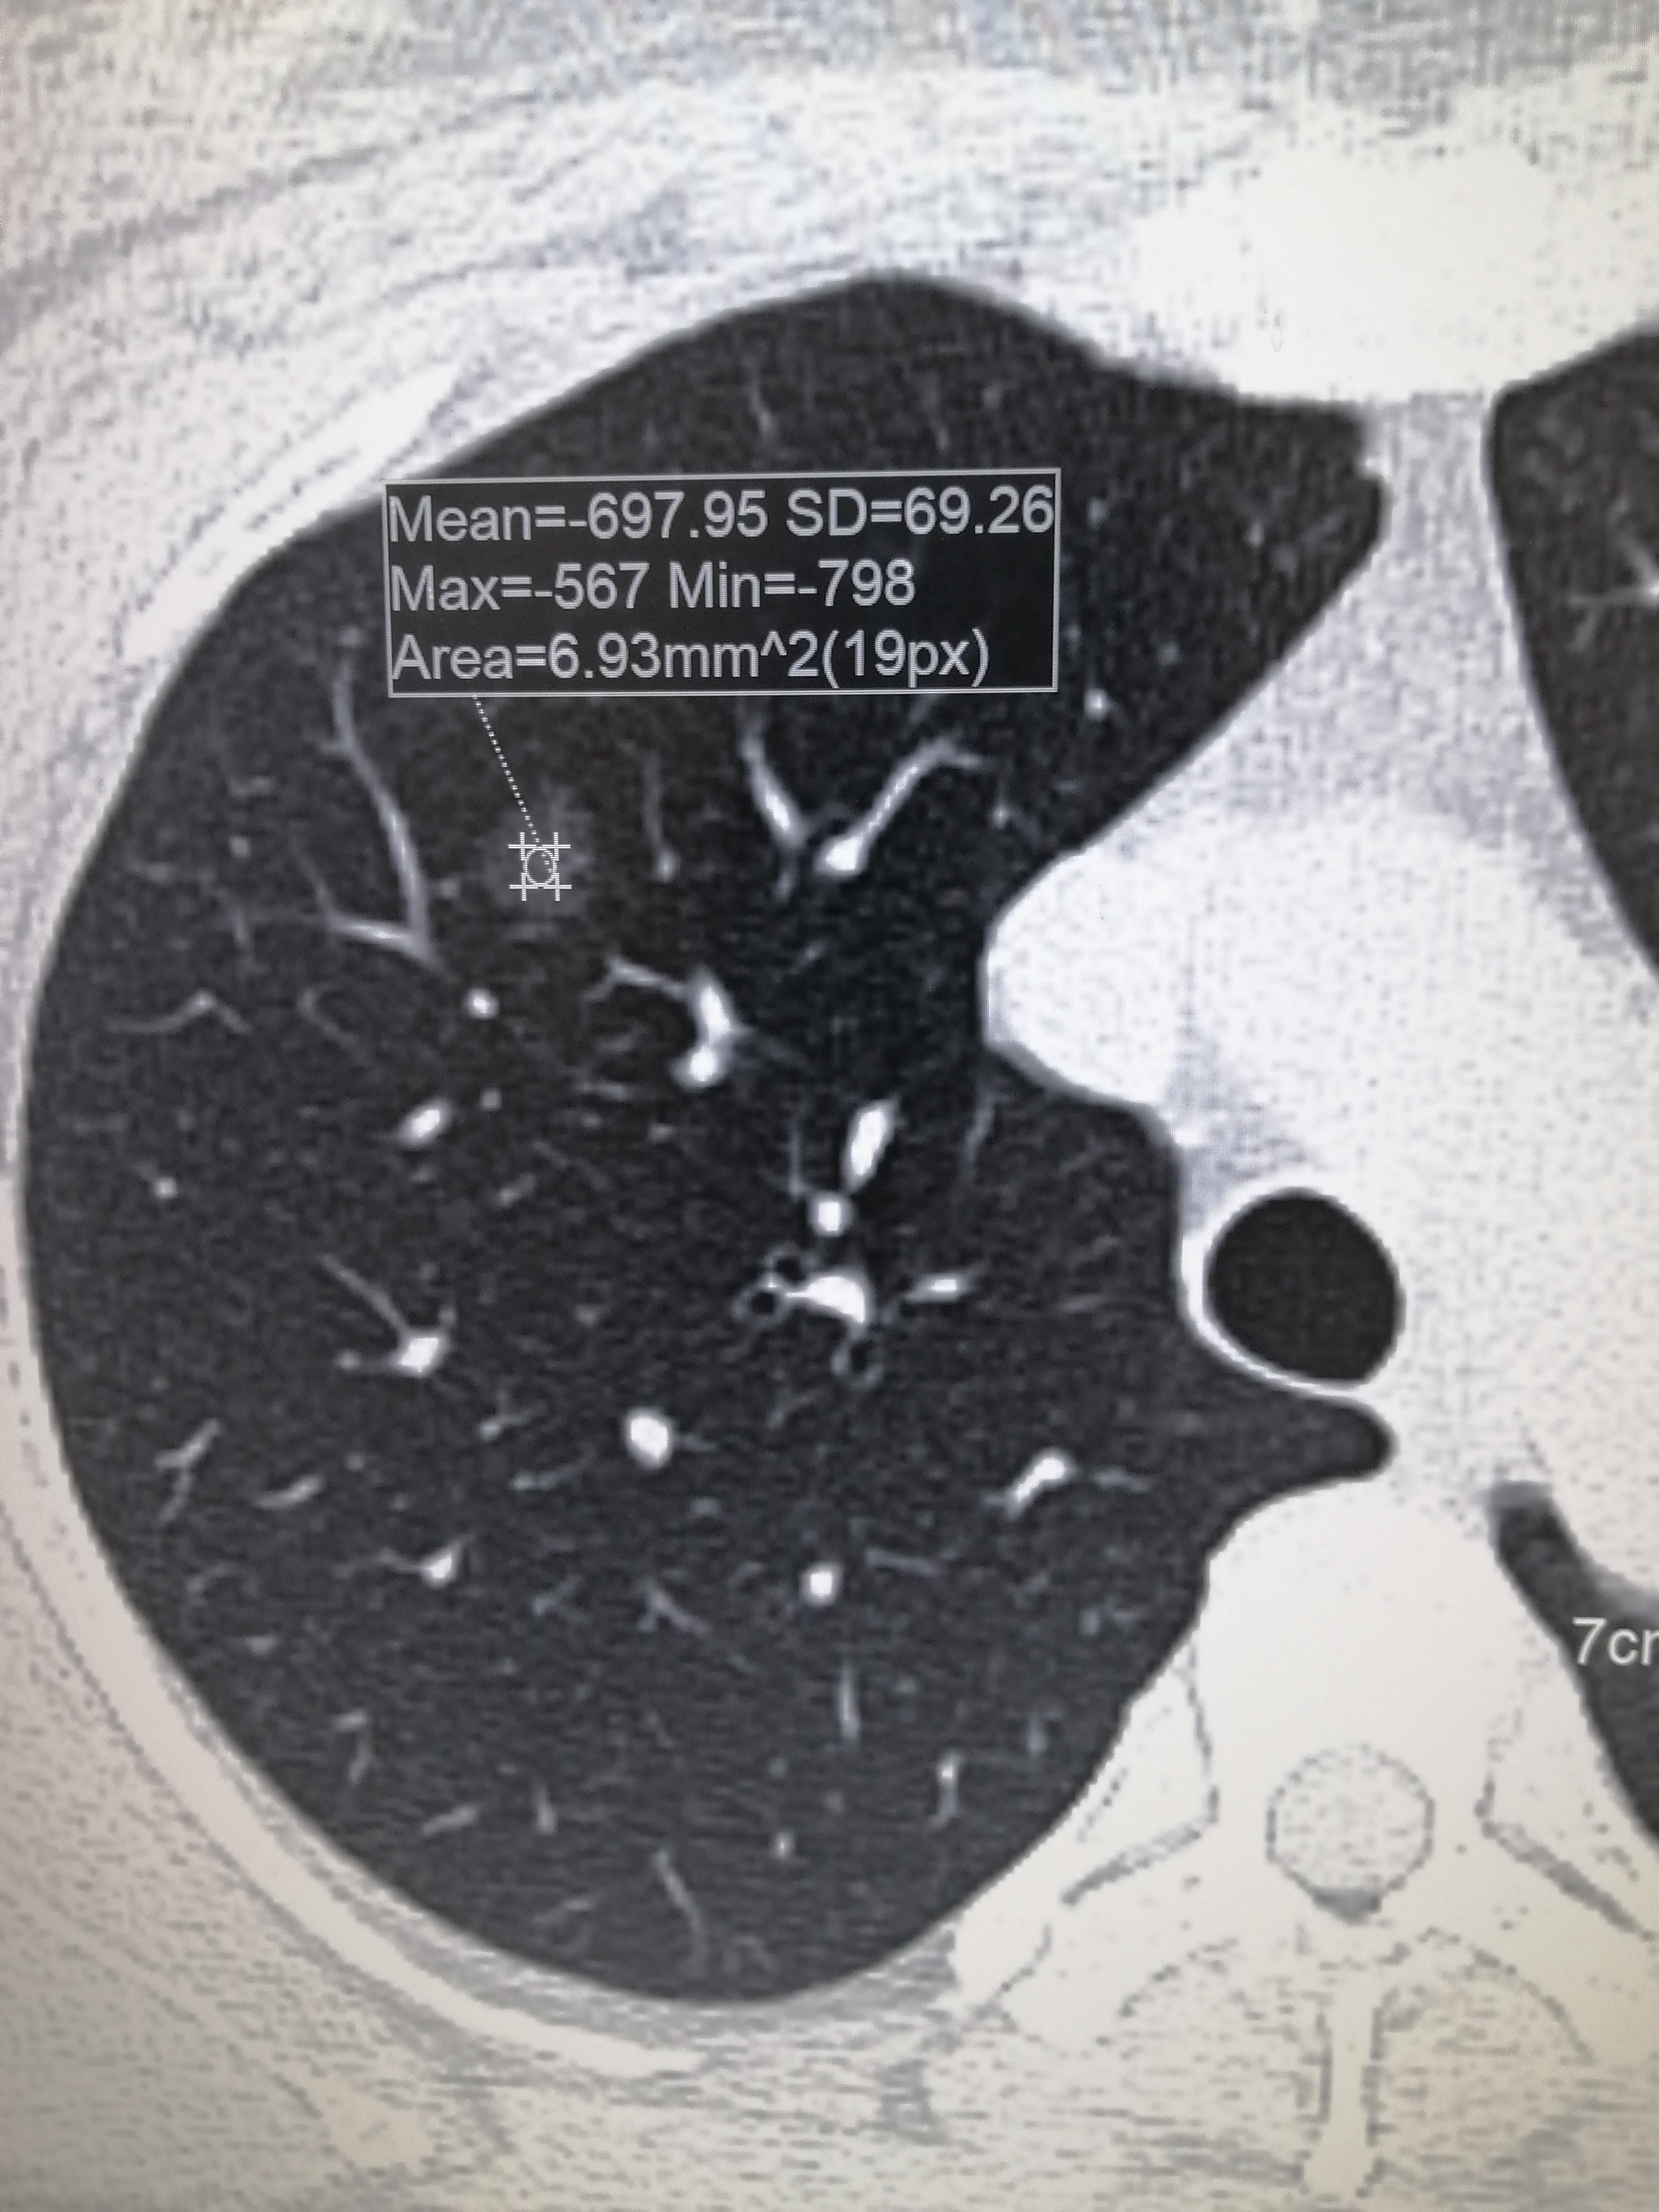

右肺上叶磨玻璃结节7mm

1、对于7mm的磨玻璃结节是否可以进行微波消融,需根据结节性质分情况讨论若结节为良性,一般不建议进行微波消融良性磨玻璃结节通常生长缓慢,对肺功能影响较小,且恶性风险较低此时采取微波消融等有创治疗可能引发出血气胸等并发...